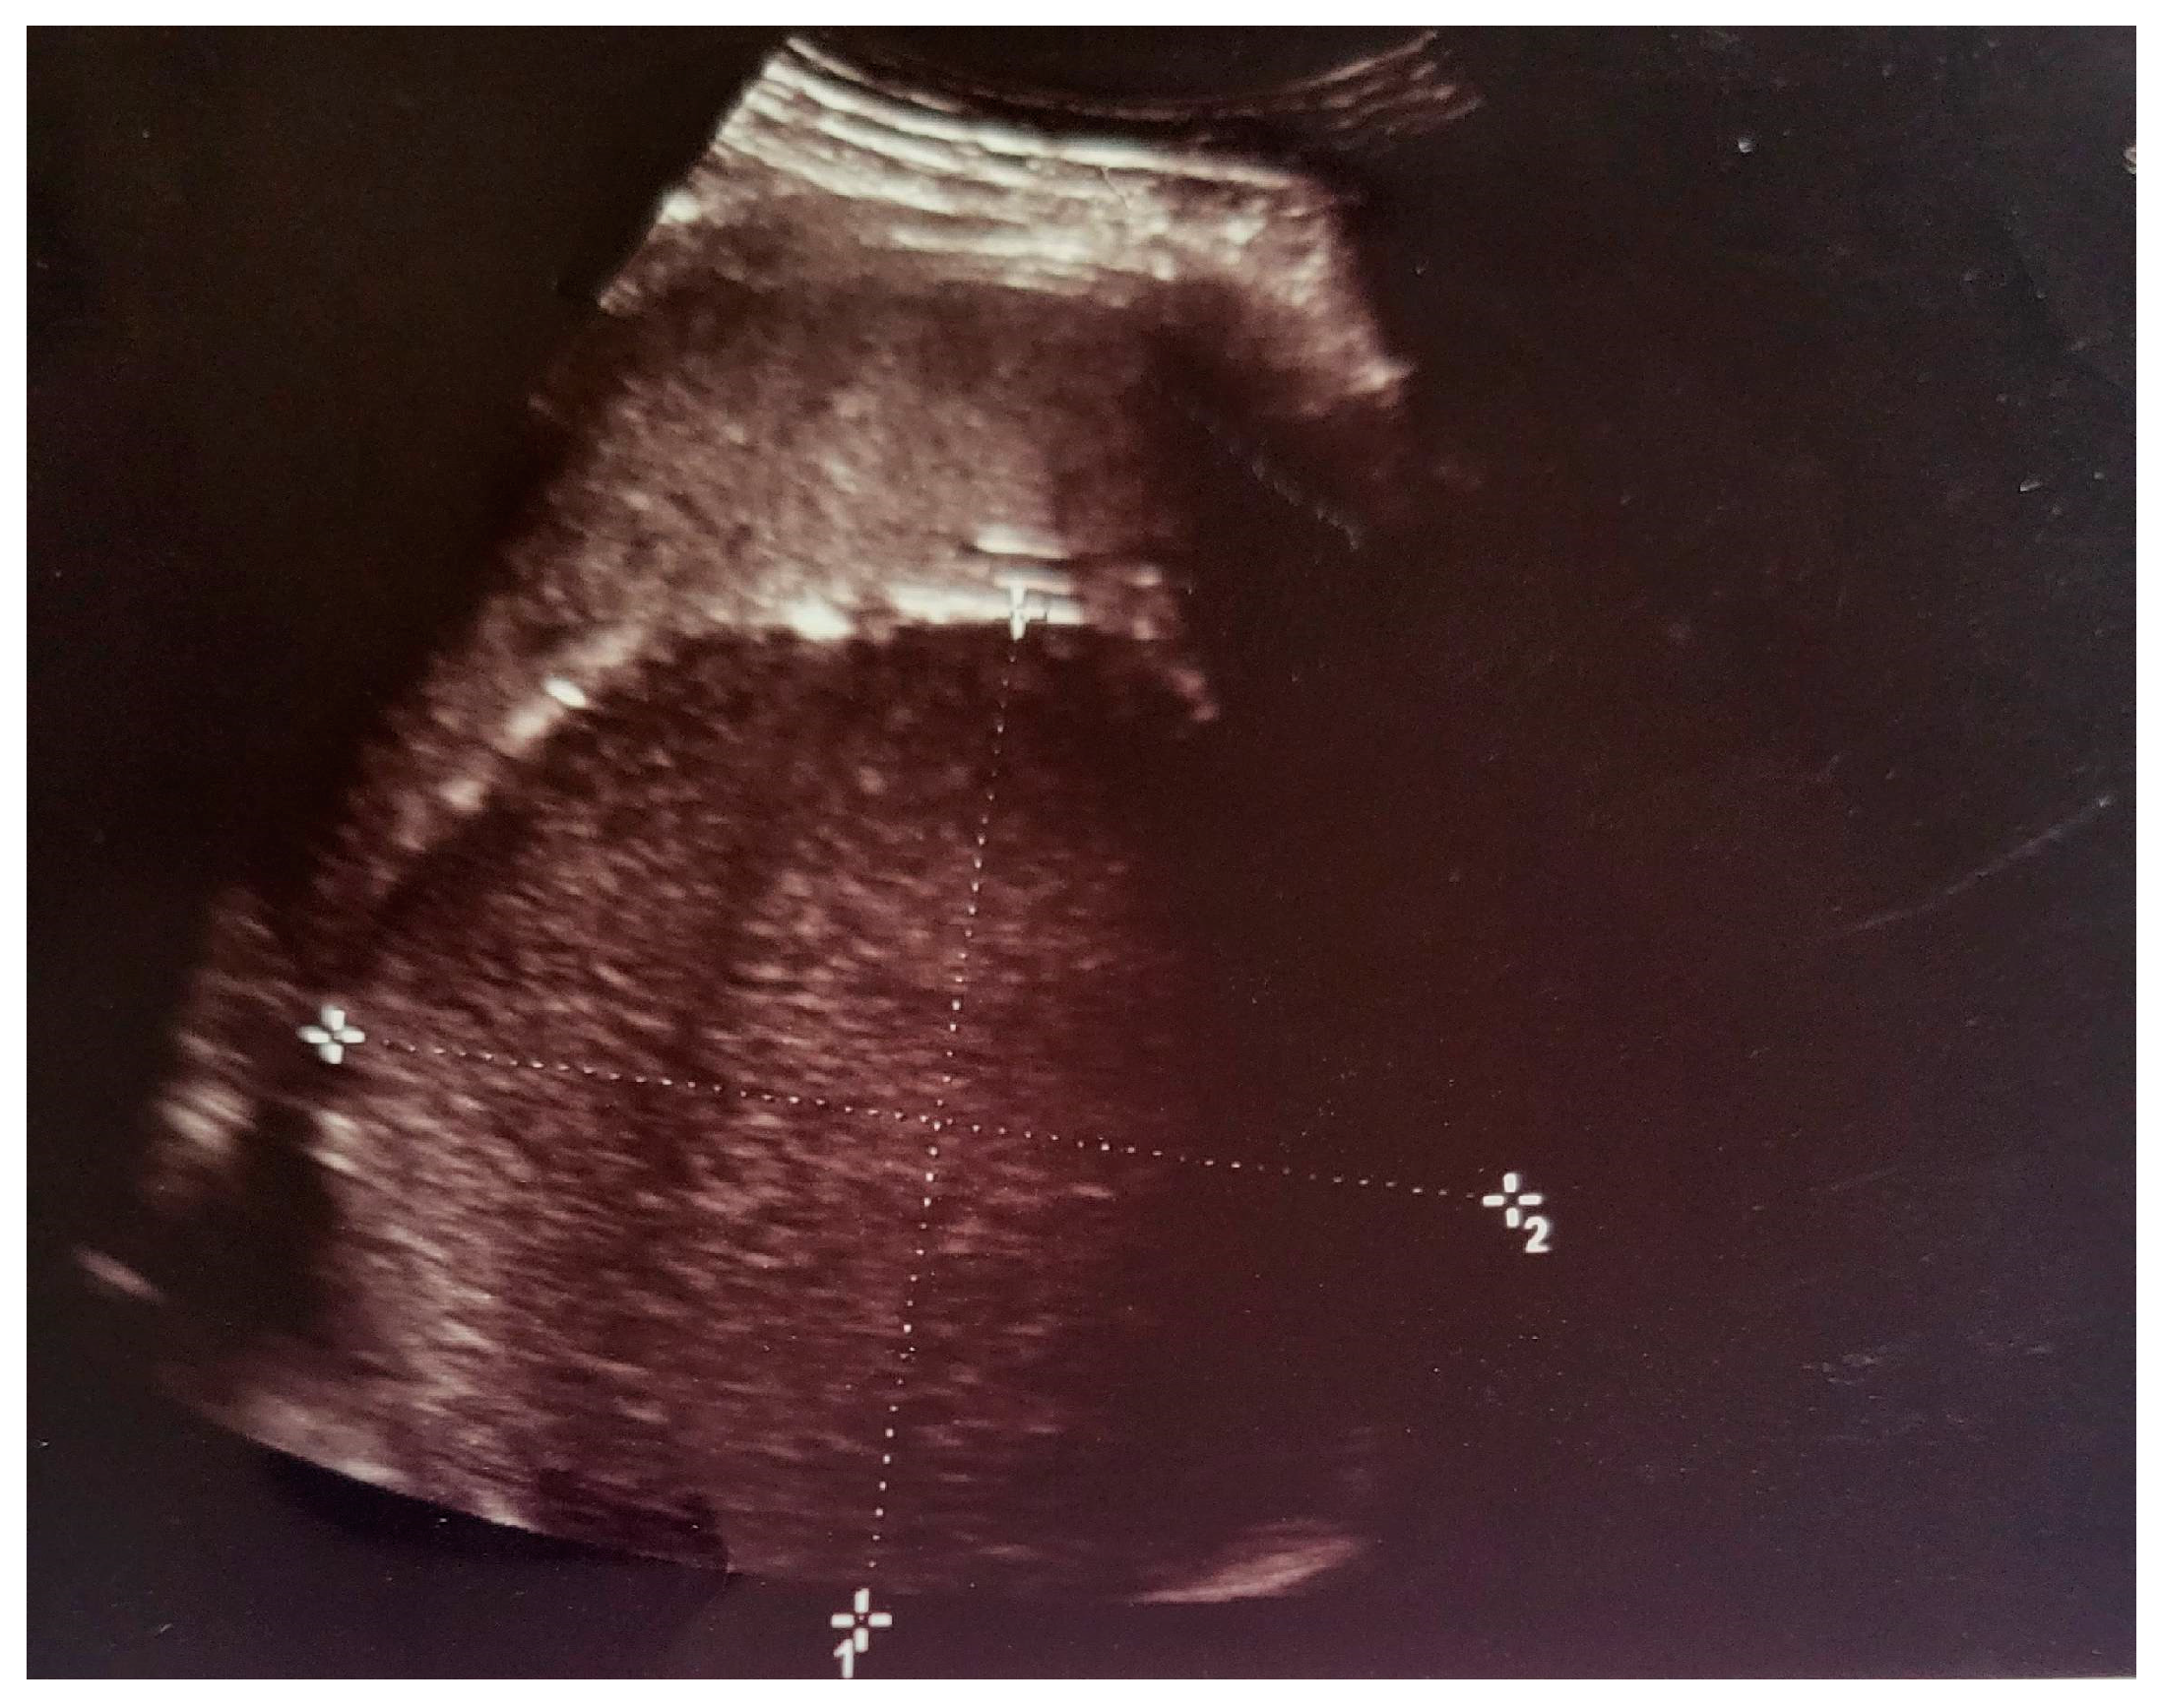

- Grade I splenomegaly with simple voluminous splenic cyst, 10 cm in diameter.